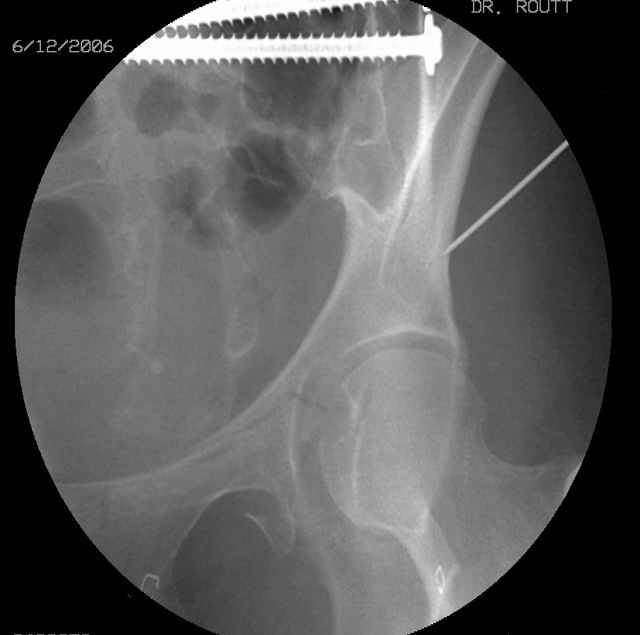

We seek the starting site (after reduction) with a thin wire guided by fluoroscopic imaging as the obturator-outlet combination image and also the inlet image...engage the wire tip into bone, incise around the wire, apply a soft tissue protection sleeve of known length over the wire, remove the wire, exchange thru the sleeve with an appropriate diameter drill (I use a 3.5mm most often), drill the glide pathway above and behind the joint to the fracture, exchange for a calibrated appropriate diameter drill, oscillate within the ramus to the pubis, measure depth using the calibrated drill and known sleeve length, do the math, remove the drill and insert screw, tighten, squirt the hole, close, stress the fixation, supplement if needed.